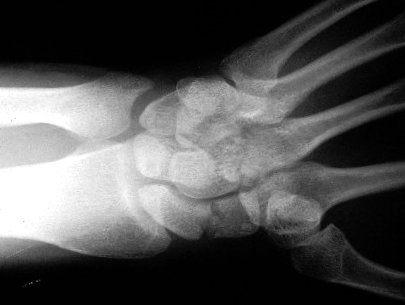

Scaphoid Xray view